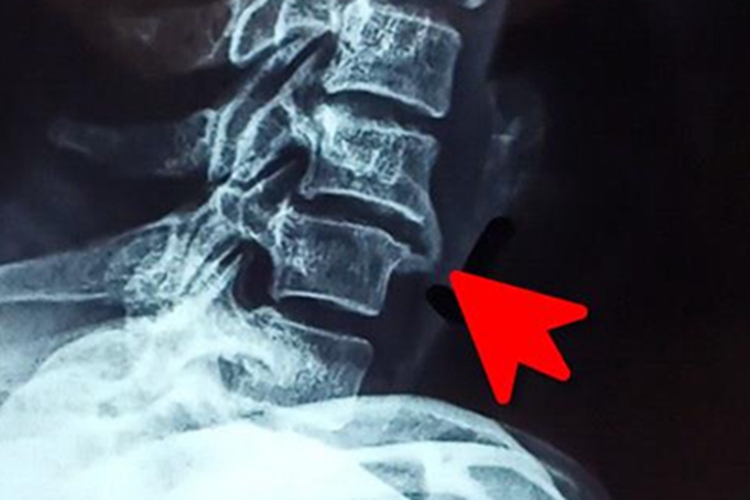

骨质增生指单位体积内骨量的增多,X线检查见骨皮质增厚、骨小梁增粗增多和骨质密度增高,可伴有骨骼的增大变形。在肌腱、韧带和骨间膜的附着部位的骨质增生常形成骨性赘生物,按其形状的不同被称为骨刺、骨桥等。